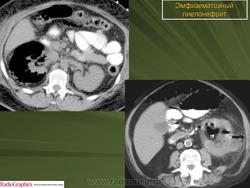

Эмфизематозный пиелонефрит

ID: 17283 Emphysematous pyelonephritis Dr Maulik S Patel - 1 Apr 2012 Emphysematous pyelonephritis

ID: 24370 Emphysematous pyelonephritis Dr Ian Bickle - 10 Aug 2013 This is a case of emphysematous pyelonephritis. This constitutes only a...

ID: 23334 Emphysematous pyelonephritis Dr MT Niknejad - 7 Jun 2013 The CT findings in a 76 Y/O diabetic patient with fever , flank pain and...

ID: 10632 Emphysematous pyelonephritis Dr Wael Nemattalla - 28 Aug 2010